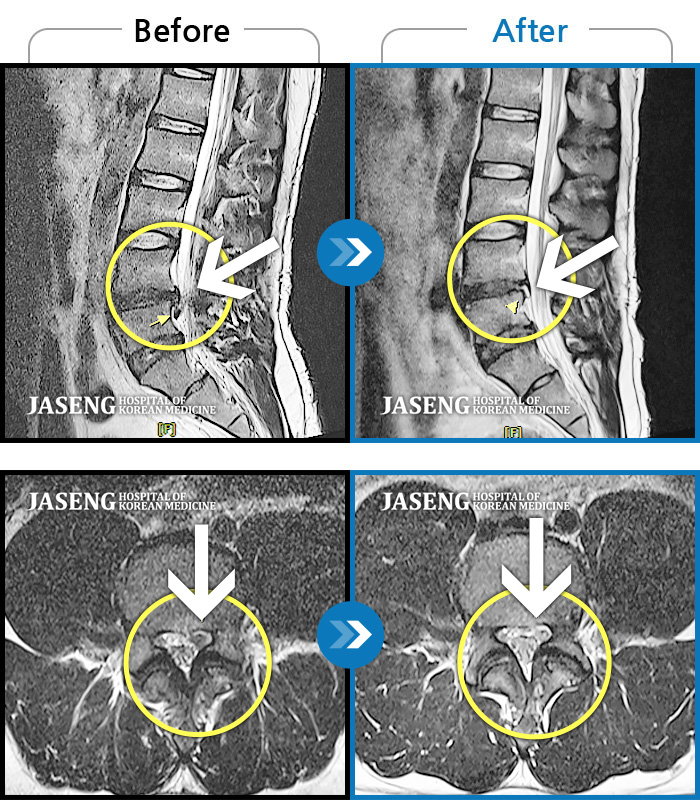

Before

After

환자에게 사전 동의를 받아 동일 조건에서 촬영되었습니다.

개인에 따라 치료 후 부작용이 발생할 수 있으니 의료진과 상담 후 치료를 진행하시기 바랍니다.

허리 통증, 야간통으로 내원

갑작스러운 허리 및 왼쪽 하지 통증으로 내원